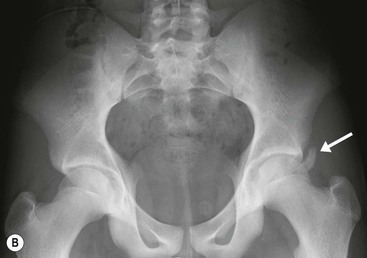

Two kinds of femoroacetabular impingement are described, cam type and pincer type, though these often coexist.20 Cam impingement is caused by the presence of an abnormal osseous ‘bump’ found on the anterior or lateral aspect of the femoral head–neck junction (Fig. 46-36). This produces abnormal contact between femur and acetabular rim in certain positions and typically presents in young athletic men. The α angle can be used to identify this loss of sphericity on a cross-table lateral radiograph or axial oblique MRI (Fig. 46-37). An α angle measuring greater than 50° may be taken as abnormal.21 Repeated contact between the osseous bump and the anterior acetabulum during hip flexion results in a labral tear and/or cartilage damage. CT is an excellent technique for demonstrating the bone morphology in this condition, although MR arthrography is able to show the cartilage and labral damage. Acetabular cartilage delamination (separation of the cartilage from the underlying bone), sometimes termed a ‘carpet lesion’, is common in cam-type impingement and may be detected on MR arthrography.22 The information provided by arthrographic MRI is important, as joint-sparing treatment (such as cam re-contouring) is unlikely to give effective symptom relief if there is established severe cartilage damage.